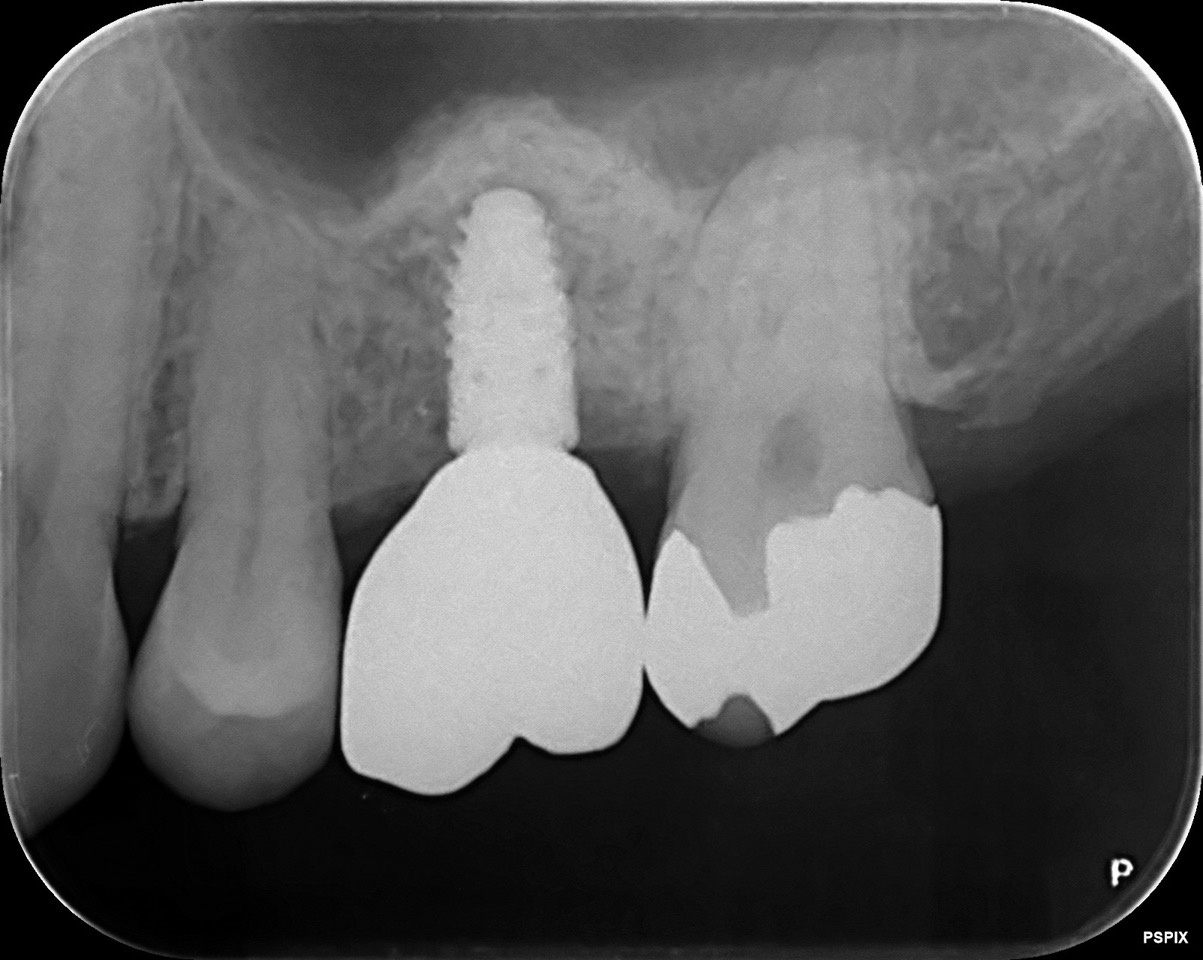

CASE 03

| 主訴 | 歯がないところにインプラントをして欲しい |

| 治療内容 | 左上6番 サイナスリフト+インプラント |

| 治療回数 | 12回 |

| 治療費用 | ¥492,000 |

| 想定される副作用 | 腫れ、痛み |